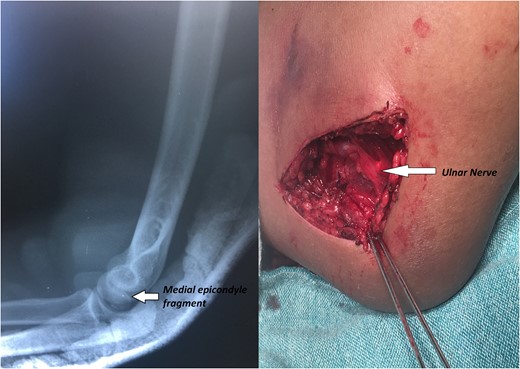

A 14-year-old male patient presented to the emergencies department complaining of intense pain in the left elbow secondary to a fall with an outstretched hand while practicing soccer. He had no significant comorbidities. At physical examination he presented with deformity located on the left elbow, he was unable to passively or actively mobilize it, he reported paresthesias and diminished sensation located on the fifth and fourth digit. X-rays showed a dislocation on the left elbow and an avulsive fracture of the medial epicondyle of the distal humerus (Fig. 1). He was taken to the operating room where a closed manipulation was performed; however the reduction was not achieved due to the interposition of the fractured medial epicondyle. A medial approach to the elbow was performed; intra-operative findings included rupture of the medial capsule and intra-articular interposition of the fragment of the medial epicondyle with a posterolateral dislocation of the elbow, the ulnar nerve showed compressive injuries at the site of the fracture (Fig. 2). Extraction and fixation of the interposed intra-articular fragment was performed followed by elbow reduction and a medial capsule repair, without ulnar nerve transposition (Fig. 3). The patient was left with a posterior splint for a month. After a 3 month follow-up, he has recovered full range of motion of the elbow with recovery of strength and sensation over the distribution of the ulnar nerve.

X-rays showing the result of the first attempt of closed manipulation and open reduction.